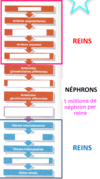

Quelles sont les 3 zones du rein?

- externe (cortex rénal)

- intermédiaire (médullaire rénal ou médulla)

- interne (bassinet)

Que comprend la zone intermédiaire du rein et sa fonction?

- comprend tout les pyramide rénal (trait)

- chargé de retenir l’urine par la terminaire des pyramide (les papille rénal)

Que comprend la zone interne du rein et sa fonction?

interne (bassinet) retient l’urine avant de se déverser dans uretere, calice mineur sont à la terminaison des papile rénal et tous les calice mineur se réunisse pour former le calice majeur